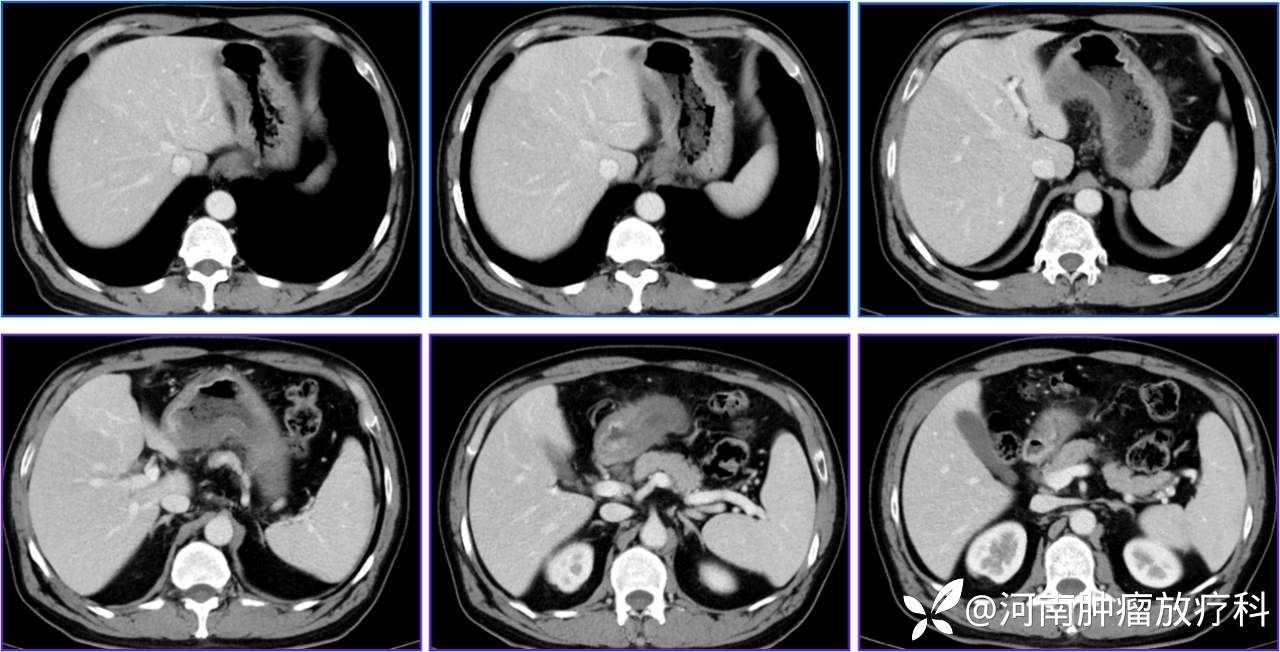

CT:2022.09.12(颈部至盆腔):胃壁增厚,粘膜层强化明显,胃窦显著。胃窦周围多发小淋巴结。

PET-CT(2022.9.12):胃体小弯侧及胃窦不均匀增厚,代谢高,符合胃癌表现。腹腔、肝胃间及胃壁周围多发软组织结节影,淋巴结转移不除外。余未见明显异常。